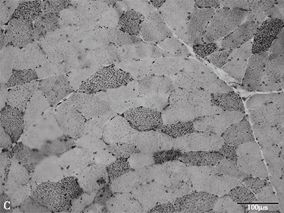

1小时条评论【病例资料】 患者,女性,40岁,公司职员。因左下肢肿痛1年,加重伴双肘、腕肿痛1个月,于2007年10月25日收入北京医院免疫内科。 现病史:患者于2006年10月无明显诱因出现左小腿肌肉痉挛,多于夜间发作,疼醒后自行牵拉肌肉可以缓解疼痛,2~3天发作1次,此后左...